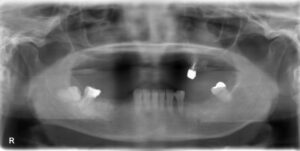

上下顎4本欠損症例

BEFORE AFTER 71歳女性/上下顎4本欠損/インプラント埋込手術 【治療内容】 左上、左下共にブリッジが入って…